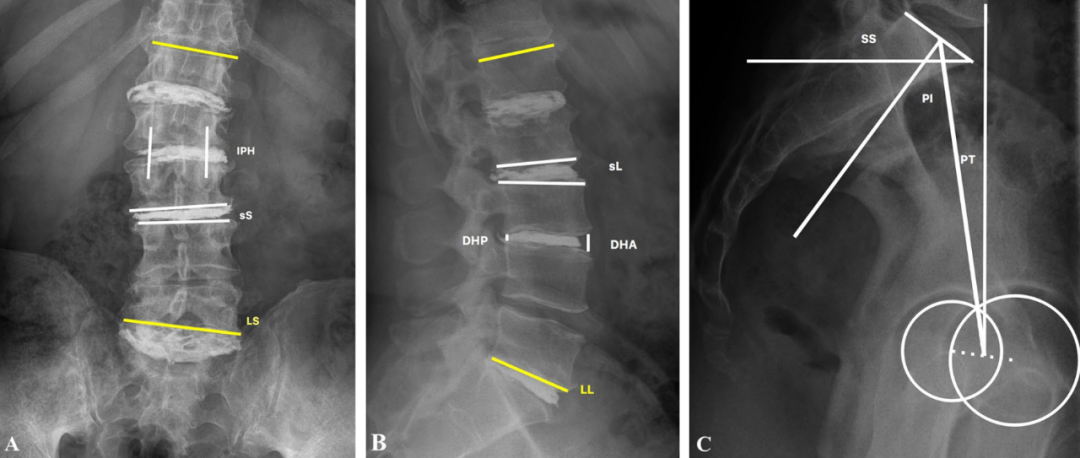

适应症:1. 老年患者,通常应大于75岁;2. 典型机械性腰痛,站立时加重,卧床休息或佩戴支具(主诉);3. 动力位片、站立和仰卧位X线片或站立X线和CT片提示腰痛与椎间盘高度变化相关,也称为手风琴现象(accordion phenomenon);4. 椎间盘真空征5. 1个或多个节段的脊柱畸形或退行性椎体滑脱且因高手术风险、不能耐受开放手术者

图: 典型的手风琴现象左图为站立位X线片,右图为仰卧位CT。站立位负重时的椎间盘与仰卧位(不负重)椎间盘塌陷程度不同,且侧凸角度也不同(分别为25°和14°)

值得一提的是,仅仅存在椎间盘真空征不是PCD的适应症(因为大多数真空征是无症状的),如果椎间盘内真空征伴随手风琴现象,则提示存在椎体节段不稳,可考虑行PCD。